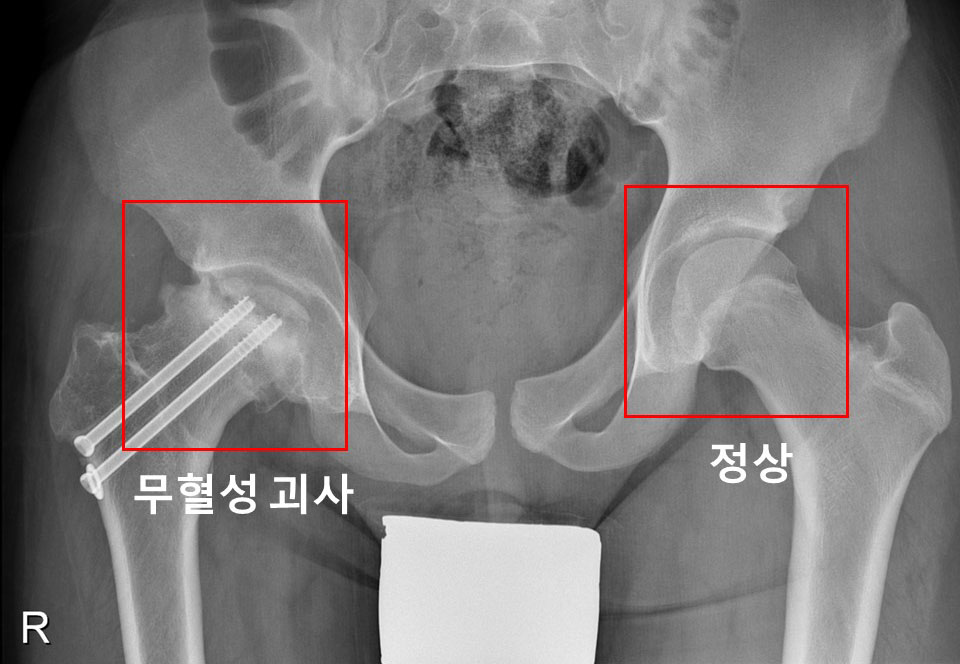

우측 고관절에 대퇴골두 골단 분리증 및 무혈성 괴사가 발생한 소아청소년 환자의 X-ray

[사진] 우측 고관절에 대퇴골두 골단 분리증 및 무혈성 괴사가 발생한 소아청소년 환자의 X-ray

대퇴골두 골단 분리증은 대퇴골 위쪽 성장판 부위에서 대퇴골두와 그 아래의 뼈가 특별한 외상 없이 분리되는 병이다. 진단이 지연될 경우, 대퇴비구 충돌증후군 혹은 대퇴골두가 썩는 대퇴골두 무혈성 괴사가 발생할 수 있다.